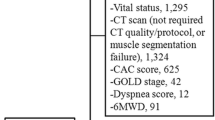

We identified patients aged ≥18 years with a diagnosis of breast cancer, sarcoma, or lymphoma who received anthracyclines and/or trastuzumab-based chemotherapy at the University of Minnesota MHealth Fairview between 2009 and 2014. Eligible patients had to have two CT scans, with a baseline CT scan within 6 months prior to chemotherapy initiation and the second (follow-up) CT scan within 2 years after chemotherapy initiation. All patients with sarcoma or lymphoma had received anthracycline; individuals with breast cancer had received anthracyclines, trastuzumab, or both. Individuals with a cardiac event prior to chemotherapy were excluded. Chart abstraction was performed to confirm specific diagnoses, staging, treatment regimen, duration of therapy, and date of CT scans before and after chemotherapy. The institutional review board of University of Minnesota approved this retrospective study.

A total of 474 patients were included in our analysis (breast cancer n = 192, lymphoma n = 184, sarcoma n = 98), of which 161 (34%) male and 234 (53%) had stage IV cancer (Table 1). Median age at the time of baseline CT scan was 61 years. Almost all patients received anthracyclines except 12% who had trastuzumab only. Most (91%) of all patients had their follow-up CT scan within a year after starting chemotherapy, and 87% within a year after their baseline CT scan. Median baseline PMI of total cohort was 5.8 cm2/m2 (4.9, 7.7) which on average decreased 10.5% after chemotherapy, to 5.2 cm2/m2 (4.4, 6.4). Median baseline PMI was 5.3, 6.5 and 6.7 cm2/m2 which after chemotherapy decreased to 5.6, 12.3 and 17.9% in Breast cancer, lymphoma and sarcoma respectively.

Among 325 patients treated with curative intent, 93 died from all-cause mortality (17, 62, and 14 with breast cancer, lymphoma and sarcoma respectively) with a median follow-up time of 5.5 years. There were 49 MACE, (13, 35, 0) in breast cancer, lymphoma and sarcoma respectively. In the competing risks analysis of death from non-cardiac causes as competing event, the small number of MACE (only 48) limited the number of covariates we could adjust for, therefore only age and sex were included in this regression model.